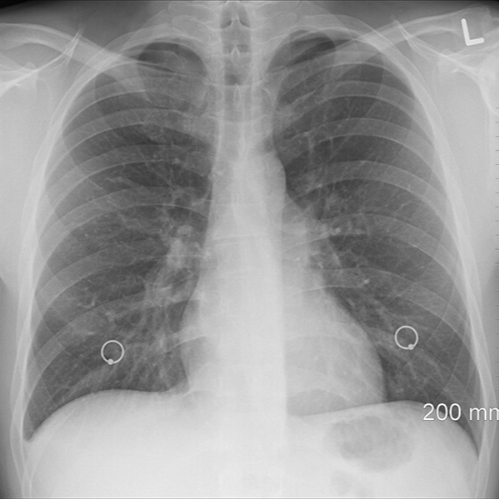

폐렴이 의심되면 가장 먼저 흉부 X-Ray 검사를 하는데 흉부 X-Ray 촬영으로 하는 검사는 폐렴이 얼마나 진행되었는지도 보여 줍니다. 그러나 흉부 X-Ray만으로 뚜렷한 폐 음영이 보이지 않으면, 흉부 CT(전산 단층촬영) 검사를 하기도 합니다. 가래를 모아 균을 배양하여 폐렴을 일으킨 원인을 찾아내며, 좀 더 정확한 진단을 위해 소변과 혈액검사를 합니다. 폐렴이 의심되면 호흡기내과, 소아청소년과에서 진료를 받을 수 있습니다.